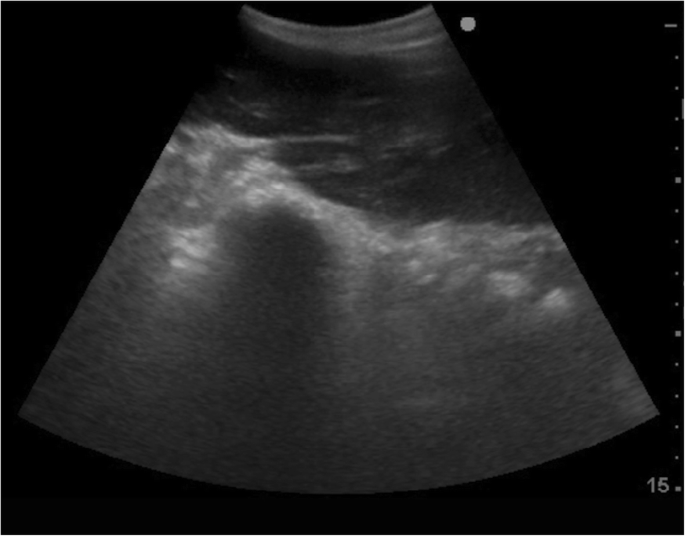

An abdominal ultrasound examination was performed. The fibre was not clipped, but rather parted at the skin, and surgical spirit was applied directly to the skin of the abdominal body wall. The caudal pleural interface and liver were first imaged through the ninth, tenth and eleventh intercostal windows, with no abnormalities identified. Within each of these spaces, the probe was moved ventrally until the third stomach compartment (C3) could be imaged. No disruption to the integrity of the wall of C3, indicative of TCU, nor any extracompartmental fluid or gas suggestive of perforation of the compartment, could be imaged. Small intestinal loops were imaged caudal to C3. Motility was subjectively reduced. An elongated, irregularly outlined mass was identified in the right ventral abdomen, adjacent to the abdominal wall (Fig. 3). The appearance was similar to hepatic parenchyma but was mildly heterogeneous in echogenicity. When the probe was moved cranially along the mass, it appeared contiguous with the liver, but protruded caudal to the costal arch. In new world camelids, the liver is normally only visible intercostally [11]. The kidneys, intact bladder, spleen and wall of C1 were also imaged, with no abnormalities detected. No excessive free peritoneal fluid was detected during the ultrasound examination.